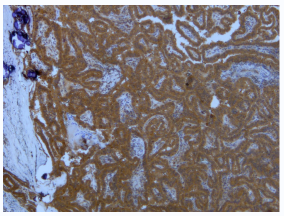

Anti- BRaf(V600E) Mouse Monoclonal Antibody

貨號26039

規(guī)格100ul